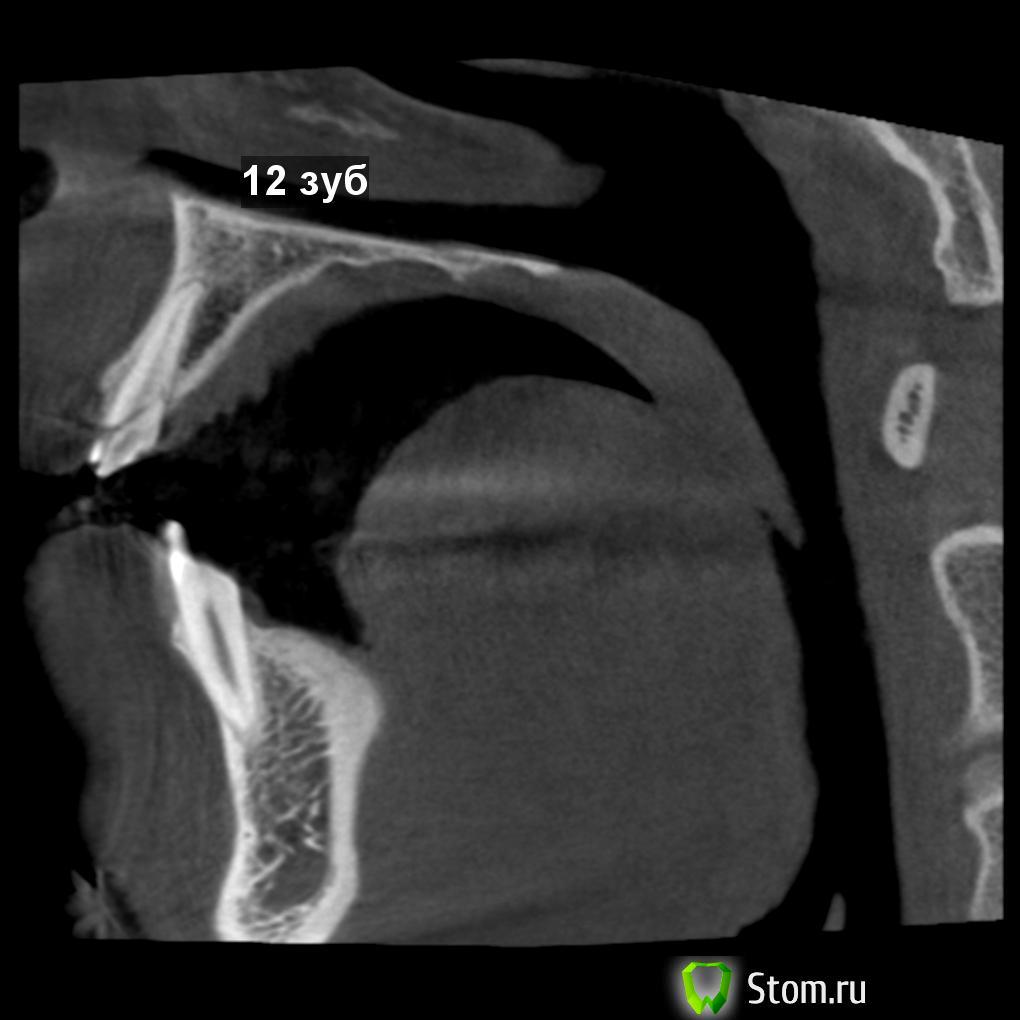

vitaliiPV Опубликовано 11 марта, 2012 Поделиться Опубликовано 11 марта, 2012 Здравствуйте уважаемые доктора. Поделитесь мыслью чтоб Вы сделали .Парню 20 лет , травме несколько дней. Подобных случаев у мене было мало, опыта в таком лечении тоже.Склоняюсь к удалению, хир. удлинение думаю нельзя из за коротких корней.Прислушаюсь ко всем комментариям.Помогите парню вернуть улыбку. Извините за качество фото снимал на телефон. После удаления отломка.12 зуб11 зуб Ссылка на комментарий